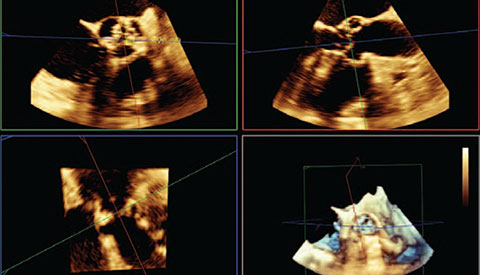

تم تشخيص أحد المرضى لديك بتضيّق في الصمام الأورطي المصحوب بأعراض. يبلغ عمر المريضة 85 عامًا وهي تعاني من السكري وارتفاع ضغط الدم. أنت تدرك خطورة وضعها الصحي ما يجعلها غير مناسبة لجراحة القلب ولكن يسمح لها بأن تكون مرشحة لاستبدال الصمام الأورطي باستخدام القسطرة (TAVR). في يومنا هذا، تمنح حلول التصوير المبتكرة والأجهزة التي تعمل عن طريق الجلد الأمل لبعض المرضى الذين لا تتوفر لهم حتى الآن أي خيارات علاجية أخرى.